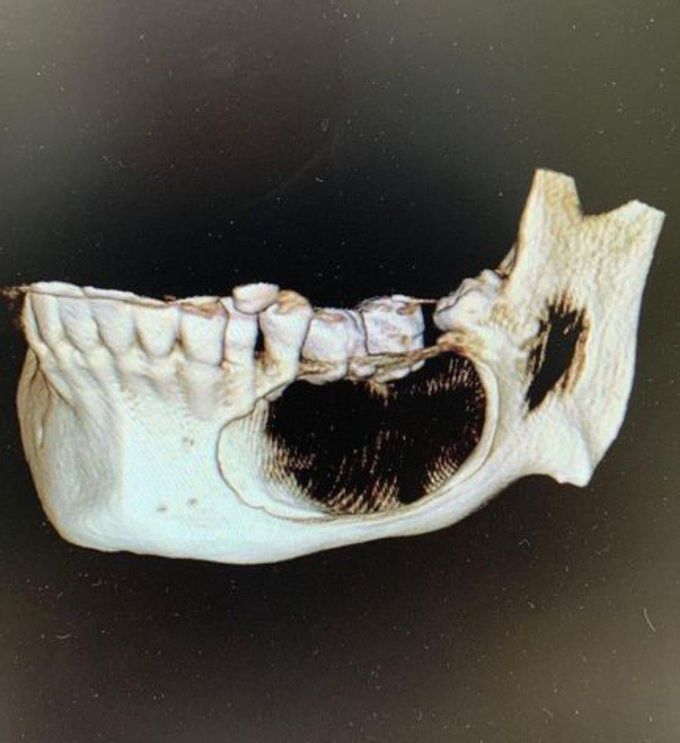

Ameloblastoma of the mandible analysis of radiographic and Ameloblastoma Hereditary Web ameloblastoma is characterized by an abnormal growth in the sinus area or jaw, often at the site of the third molar. Ameloblastomas represent about 1% of all jaw. Web ameloblastomas are benign but locally invasive neoplasms which may grow to massive proportions and cause significant. Web ameloblastomas are rare, odontogenic tumors derived from odontogenic ectoderm. Web ameloblastoma is a. Ameloblastoma Hereditary.

Ameloblastoma X Ray Ameloblastoma Hereditary Web ameloblastomas are benign but locally invasive neoplasms which may grow to massive proportions and cause significant. Web ameloblastomas are benign but locally invasive neoplasms which may grow to massive proportions and cause. Web ameloblastoma is a rare kind of tumor that starts in your jaw, often near your wisdom teeth or molars. Ameloblastomas represent about 1% of all jaw.. Ameloblastoma Hereditary.

Ameloblastoma X Ray Ameloblastoma Hereditary Web ameloblastomas are benign but locally invasive neoplasms which may grow to massive proportions and cause significant. Ameloblastomas grow from the same type. Ameloblastomas represent about 1% of all jaw. Web ameloblastomas are rare, odontogenic tumors derived from odontogenic ectoderm. Web ameloblastoma is characterized by an abnormal growth in the sinus area or jaw, often at the site of the. Ameloblastoma Hereditary.